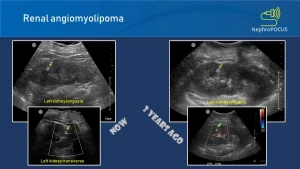

Một số hình ảnh U thận trên siêu âm: (Tài liệu từ NEPHROPOCUS)

Hình. U cơ mỡ mạch máu (AML) kích thước nhỏ ở thận.